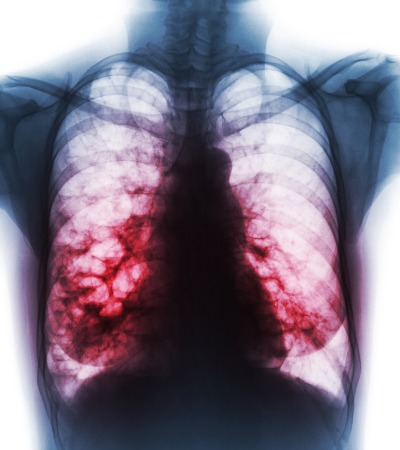

While many of the symptoms of bronchiectasis are similar to those of other conditions, some are unique to this condition. A common symptom is coughing up mucus, called sputum. The amount and color of sputum produced by individuals with bronchiectasis vary significantly. Patients with this condition tend to produce more mucus than those without it. Oren Zarif